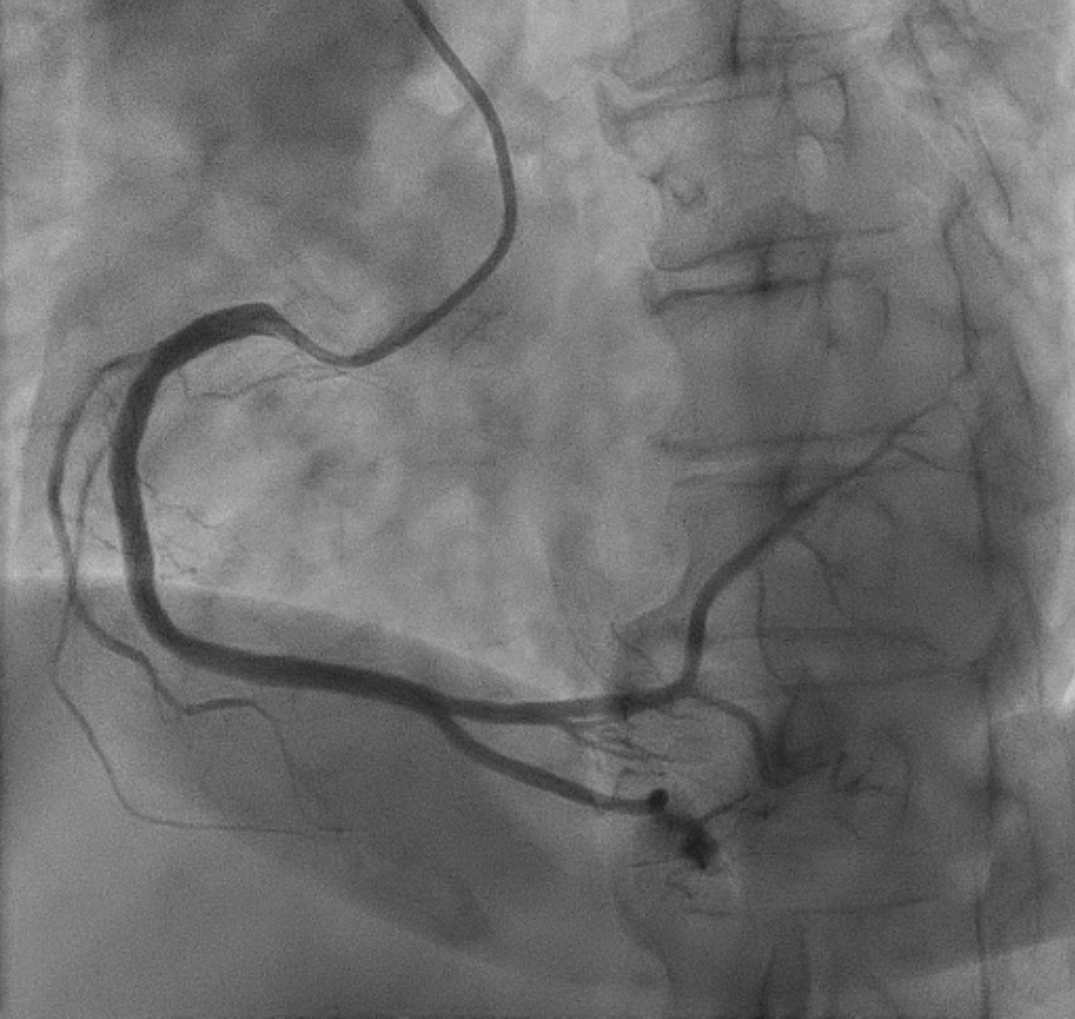

The procedure was performed using a 7 Fr right radial approach. A total of 6000 units of intracoronary heparin and 300 mg of oral clopidogrel were administered. The left coronary system was engaged with a 7 Fr extra-backup (EBU) 3.5 mm guiding catheter, and the lesion was successfully crossed with a Run-through floppy wire extending to the distal LAD. Pre-dilation was performed with a 2.0 mm x 15 mm Genoss balloon, inflated to 16 atm. Intravascular ultrasound (IVUS) imaging revealed 360-degree superficial calcium at the tight LAD lesion, a vessel diameter under 3.5 mm, and a calcium score of 2. The mid-LAD measured 3.0 mm and the proximal LAD measured 4.0 mm. Pre-dilation was performed in the mid-LAD using a 3.0 mm x 16 mm Genoss non-compliant (NC) balloon, and in the proximal LAD with a 3.5 mm x 20 mm NC Emerge balloon, both inflated to 16 atm. Post-pre-dilation IVUS imaging showed cracking of the superficial calcium with vessel expansion to 3.0 mm. Subsequently, drug-coated balloon (DCB) angioplasty was performed with a 3.0 mm x 30 mm Magic Touch DCB in the mid-LAD and a 3.5 mm x 35 mm Magic Touch DCB in the proximal LAD. Final angiography demonstrated a non-flow-limiting Type A dissection with less than 30% recoil, and the procedure was successfully concluded.